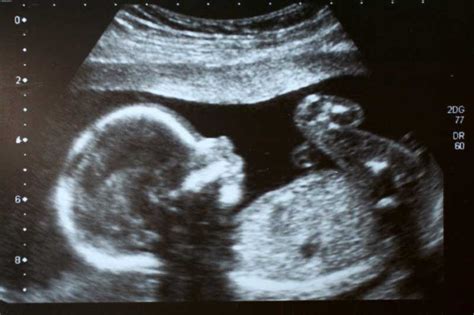

Test NIFTY je na voljo že od 10. tedna nosečnosti, kar pomeni, da ga je mogoče opraviti pred tradicionalnimi presejalnimi metodami, kot je nuhalna svetlina. Postopek je izjemno enostaven: nosečnici se odvzame le majhna količina venske krvi iz roke, podobno kot pri rutinskem laboratorijskem odvzemu. V posebnem laboratoriju se nato analizira plodova prosta DNA.